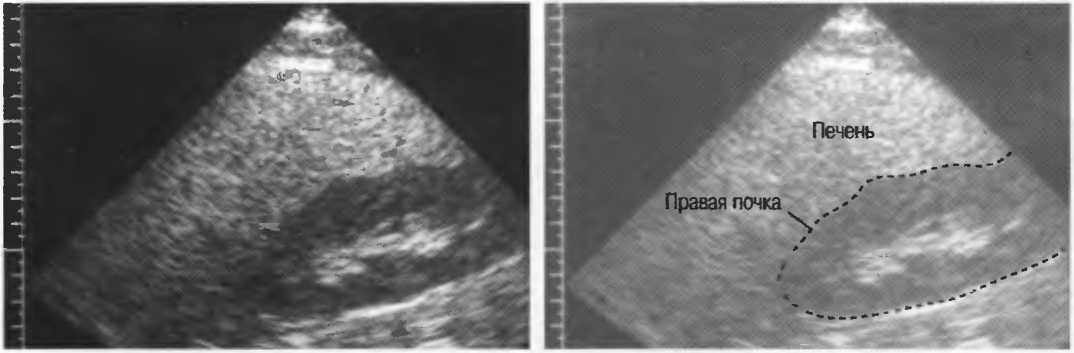

4. У здоровых обследуемых паренхима печени должна быть немного более эхогенна. чем кора рядом расположенной почки (рис. 26).

Рис.26. Продольный срез через печень и правую почку: нормальная паренхима печени более эхогенна, чем паренхима нормальной почки. Это еще один способ проверки качества изображения.